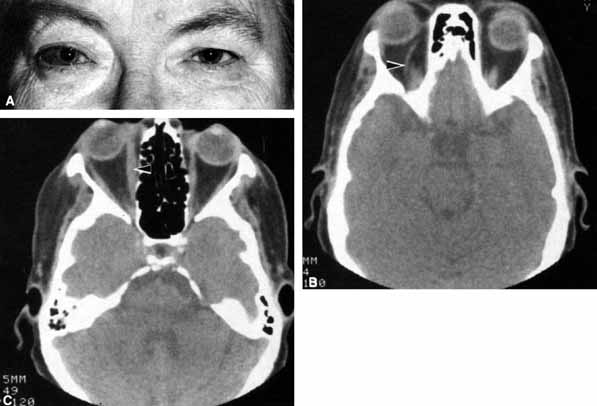

Pupillary dilation and reduction of accommodation occur when parasympathetic innervation to the globe is damaged. When the damage occurs at or distal to the ciliary ganglion, Adie's pupil results. The pupil contracts poorly to light but better to accommodation. The pupil movements are slow and poorly coordinated (vermiform). Generally there is a reduction in accommodation range. The pupil in such cases develops a supersensitivity to parasympathomimetics such as 0.1% pilocarpine. Orbital trauma, inflammation, and intraocular laser treatment may result in Adie's pupil. Deep orbital dissection lateral to the optic nerve in the region of the ciliary ganglion or around the anterior optic nerve where the short ciliary nerves run may also produce Adie's pupil. The denervation may only be sectoral, resulting in an abnormally contoured pupil which demonstrates slow tonic contracture only in the involved sector. Because the parasympathetics have diverged from cranial nerve III prior to entering the ciliary ganglion, pupillary dilation which contracts with 0.1% pilocarpine is not usually associated with neurogenic ophthalmoplegia (Fig. 19).

Fig. 19 A. A patient underwent endoscopic exploration of the right ethmoid and maxillary sinus for persistent epistaxis. Postoperatively the patient demonstrates right proptosis, restricted extraocular movements of the right eye, and a dilated right pupil. Instillation of 0.1% pilocarpine resulted in miosis on the right and no change on the left. Computed tomography (CT) shows a vessel clip lateral to the optic nerve (arrow), near the position of the ciliary ganglion. B. Coronal CT scan showing the clip lateral to the optic nerve (arrow).